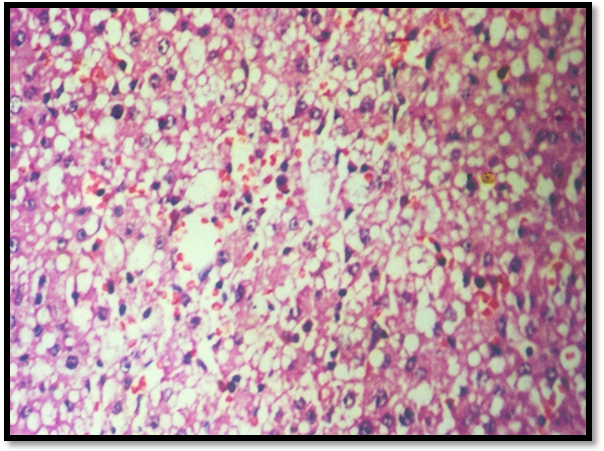

Histopathological observations

Histopathology of normal rat liver revealed prominent central view, normal arrangement of hepatic cells (Fig. 7). Microscopic examination of CCl4 treated liver section shows necrosis and fatty degeneration (Fig. 8). Liver section treated from Silymarin protected the structural integrity of hepatocyte cell membrane and recovery of hepatocyte cells (Fig. 9). Scopoletin treated group showed maximum recovery of hepatocytes, no fatty degeneration and necrosis and exhibited significant protection against CCl4 induced liver toxicity in rats (Fig. 10).

Photomicrographs of liver tissues of different groups of Albino rats

Fig. 9: Silymarin treated group